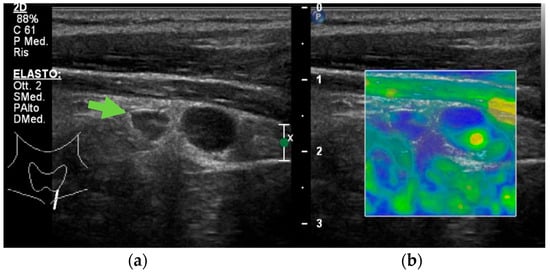

- Isidori, A.M.; Cantisani, V.; Giannetta, E. Multiparametric ultrasonography and ultrasound elastography in the differentiation of parathyroid lesions from ectopic thyroid lesions or lymphadenopathies. Endocrine 2017, 57, 335–343. [Google Scholar] [CrossRef]

- Ünlütürk, U.; Erdoğan, M.F.; Demir, Ö.; Çulha, C.; Gullu, S.; Başkal, N. The role of ultrasound elastography in preoperative localization of parathyroid lesions: A new assisting method to preoperative parathyroid ultrasonography. Clin. Endocrinol. 2012, 76, 492–498. [Google Scholar] [CrossRef]

- Cotoi, L.; Borcan, F.; Sporea, I.; Amzar, D.; Schiller, O.; Schiller, A.; Dehelean, C.A.; Pop, G.N.; Stoian, D. Shear Wave Elastography in Diagnosing Secondary Hyperparathyroidism. Diagnostics 2019, 9, 213. [Google Scholar] [CrossRef]